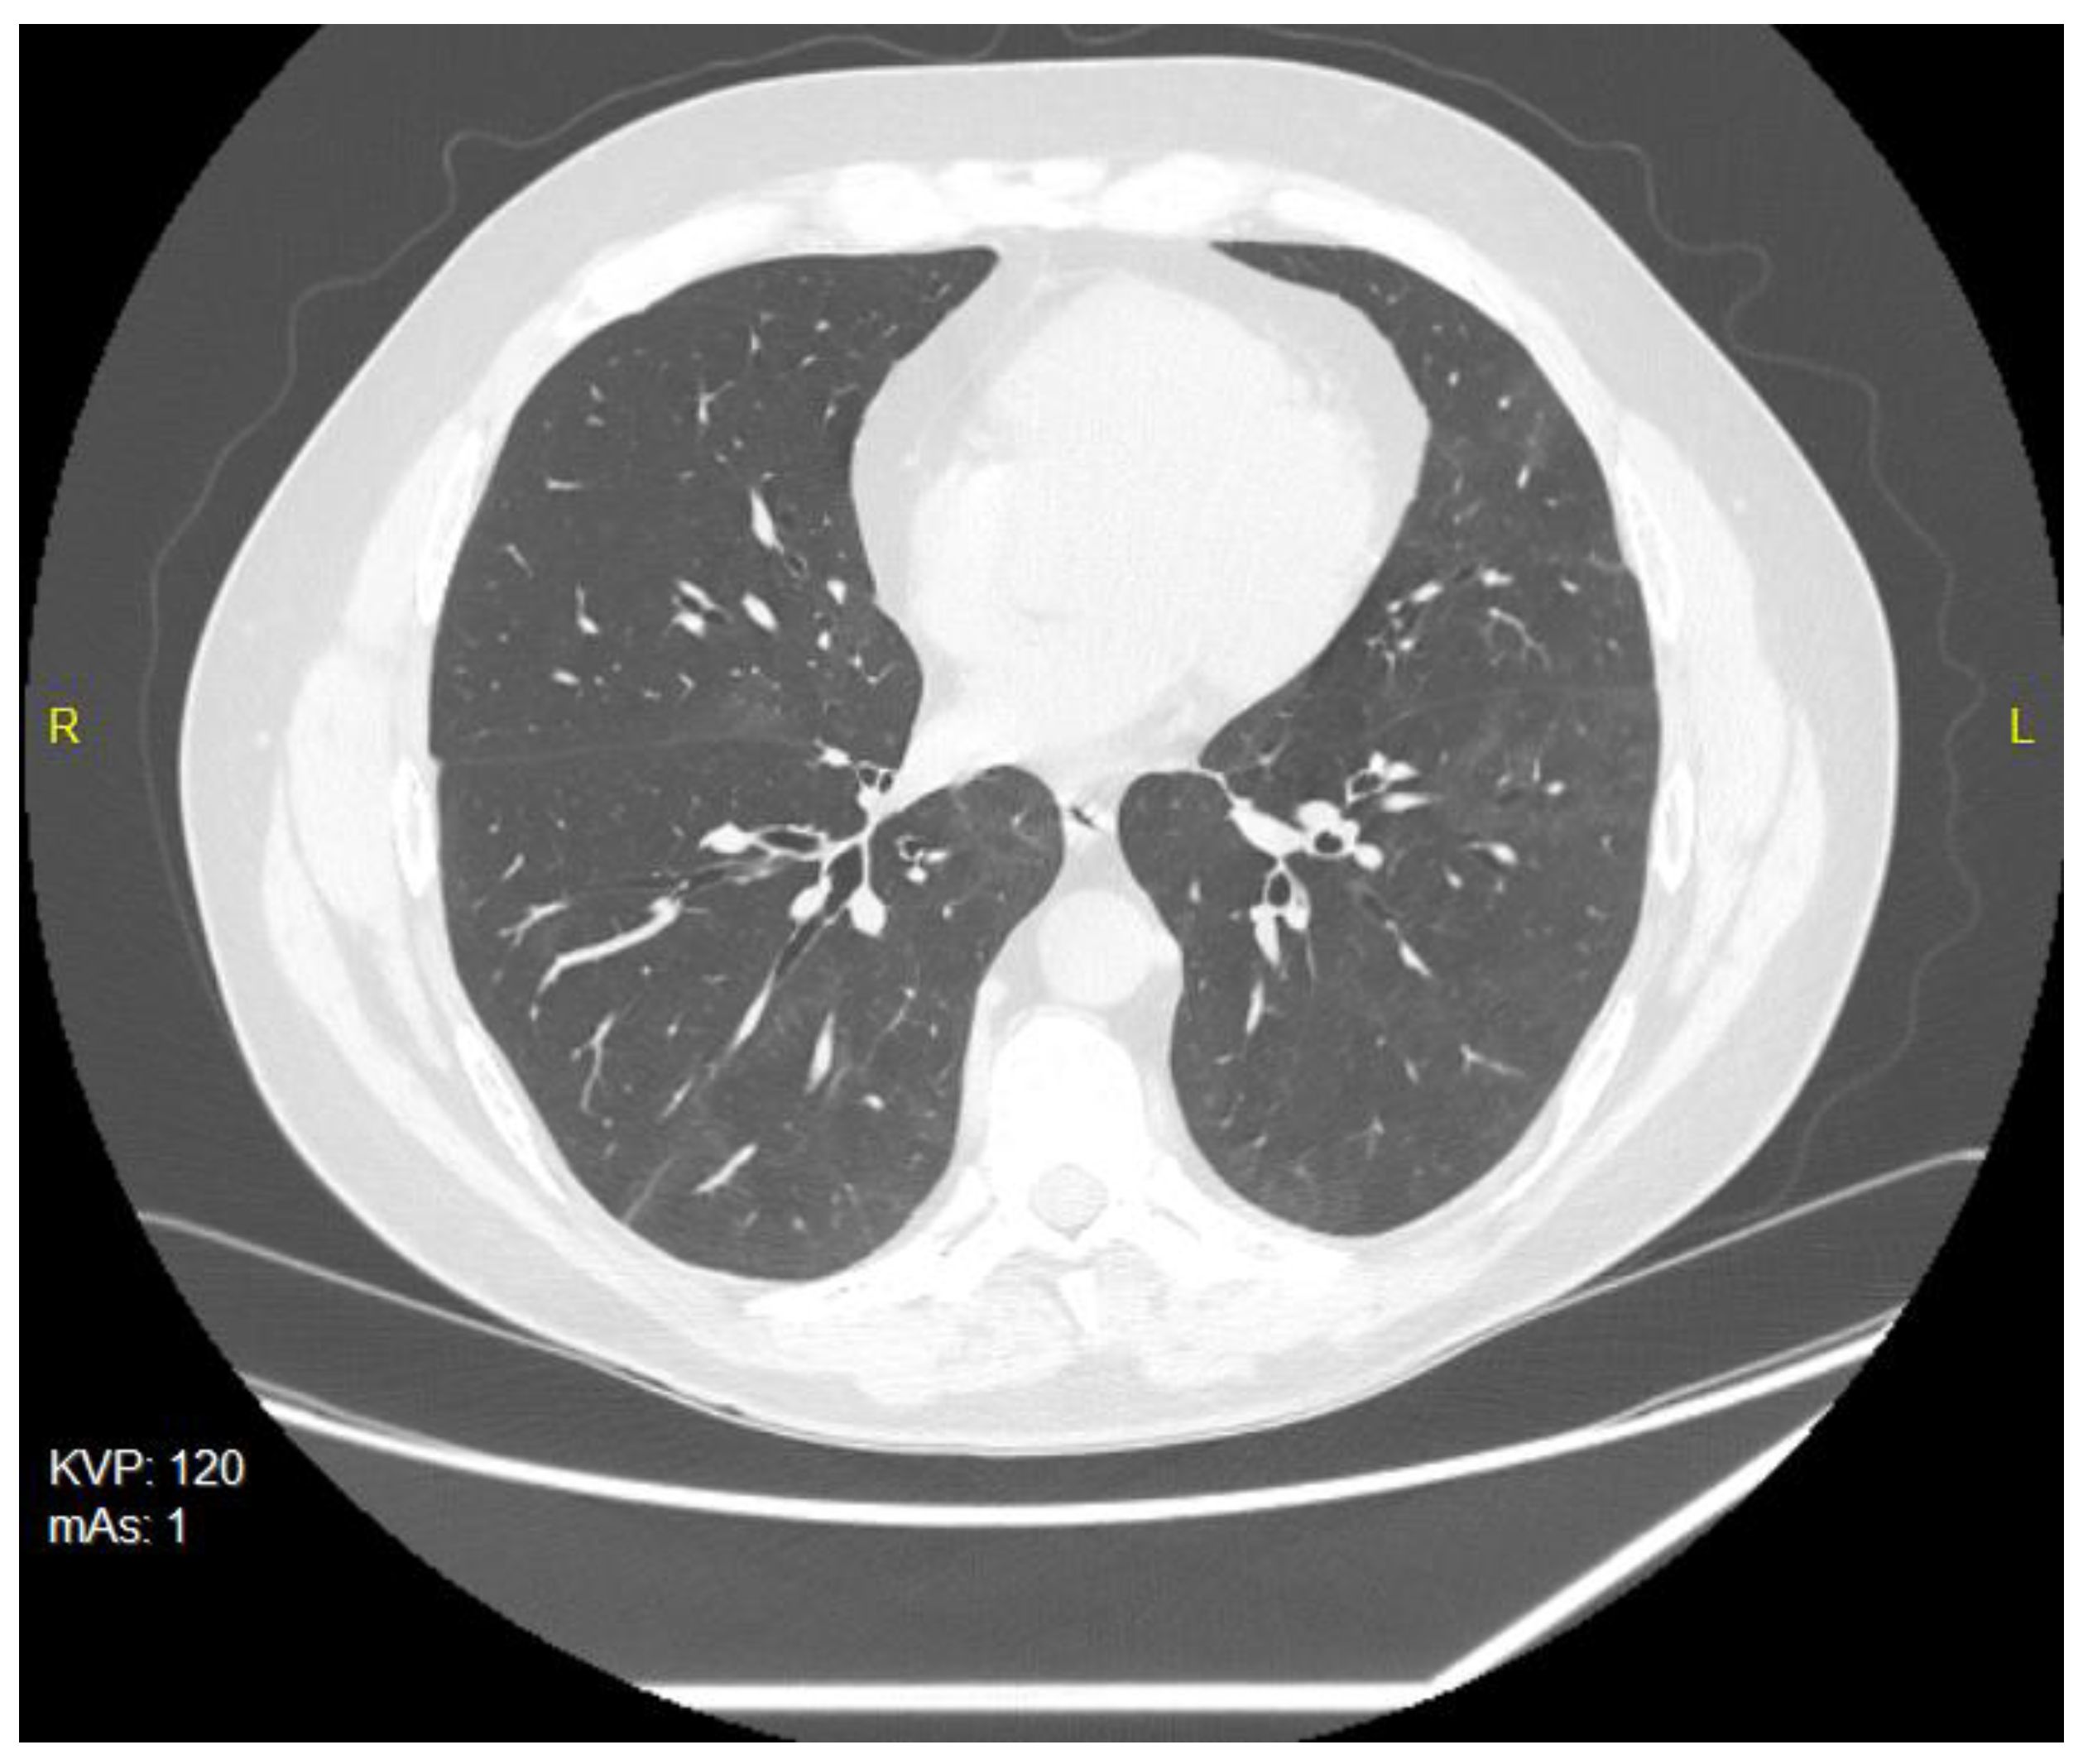

Due to the generally poor health condition, breathlessness, cough and fatigue, the patient needed to be hospitalized in a dedicated ward from 17 February 2021 to 1 March 2021. The chest X-ray performed during his hospital stay revealed consolidations of the lung parenchyma, while the CT (computer tomography) of the chest performed on 20 February 2021 showed that 55–60% of the lung parenchyma was invaded. The following control chest CT on 21 May 2021demonstrated an almost complete regression of inflammatory changes. Persistent changes included small, transient areas of ground-glass opacity, as well as linear fibrosis with traction bronchiectasis and sings of disturbed pulmonary architecture in the lower fields of both lungs and on segments of the lingula (Figure 1).

Figure 1.

CT scan of the chest of 20 February 2021—small, bilateral infiltrates of the grain-glass opacity type.